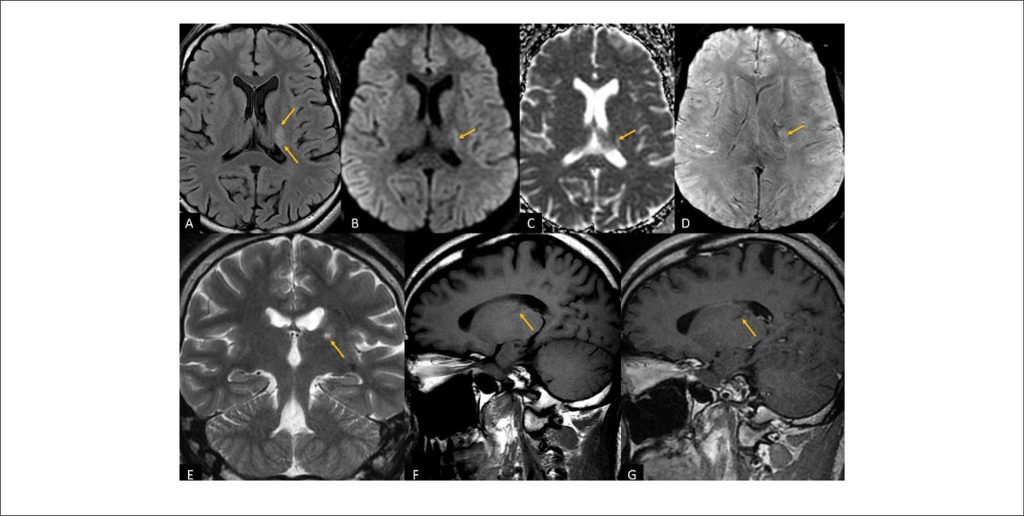

Acidente Vascular Cerebral Isquêmico em um adulto Jovem: Um Desafio Diagnóstico. Exploração da Associação entre Forame Oval Patente e Rede de Chiari

Mundialmente, os AVCs são a segunda principal causa de mortalidade, e são amplamente categorizados em tipos hemorrágicos e isquêmicos., Em 2019, o AVC isquêmico representou 62,4% dos casos, totalizando 7,63 milhões de episódios. As projeções indicam um aumento substancial na prevalência de AVC, de 3,9% em 2020 para uma estimativa de 6,4% em 2050. Apesar de investigações etiológicas abrangentes, a causa subjacente dos eventos isquêmicos cerebrovasculares permanece indefinida em 10% a 40% dos casos, conhecidos como AVC criptogênico.